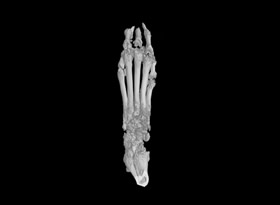

用于骨質疏松和關節(jié)炎動物模型潛伏期的骨結構和密度改變的研究。MicroCT是目前研究骨立體結構、容量和微結構細微改變較好方法。

1骨組織樣本掃描。

2提供2D圖、3D圖和相關參數(shù)的分析數(shù)據(jù)(骨密度BMD 單獨收費)。